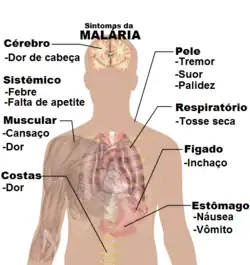

Os sinais e sintomas da malária manifestam-se geralmente entre 8 a 25 dias após a infecção.[12] No entanto, os sintomas podem-se manifestar mais tarde em indivíduos que tenham tomado medicação antimalárica de prevenção.[5] As manifestações iniciais da doença, iguais em todas as espécies de malária, são semelhantes aos sintomas da gripe,[13] podendo ainda ser semelhantes aos de outras doenças virais e condições clínicas como a sepse ou gastroenterite.[5] Entre os sinais incluem-se dores de cabeça, febre, calafrios, dores nas articulações, vómitos, anemia hemolítica, icterícia, hemoglobina na urina, lesões na retina e convulsões.[14]

O sintoma clássico da malária são ataques paroxísticos, a ocorrência cíclica de uma sensação súbita de frio intenso seguida por calafrios e posteriormente por febre e sudação. Estes sintomas ocorrem a cada dois dias em infecções por P. vivax e P. ovale e a cada três dias em infecções por P. malariae. A infecção por P. falciparum pode provocar febre recorrente a cada 36-48 horas ou febre menos aguda, mas contínua.[15]

Os casos mais graves de malária são geralmente provocados por P. falciparum, variante que é muitas vezes denominada "malária falciparum". Os sintomas desta variante manifestam-se entre 9 a 30 dias após a infecção.[13] Os indivíduos com ‘’’malária cerebral’’’ apresentam muitas vezes sintomas neurológicos, entre os quais postura anormal, nistagmo, paralisia do olhar conjugado (incapacidade de mover em conjunto os olhos na mesma direção), opistótono, convulsões ou coma.[13]